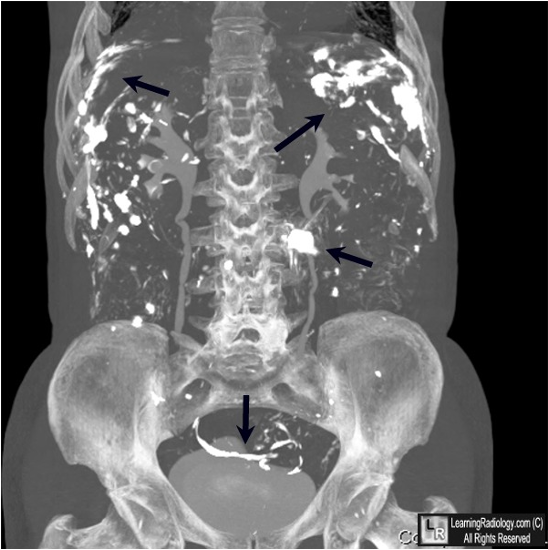

BE Perforation - Free barium in the peritoneal cavity